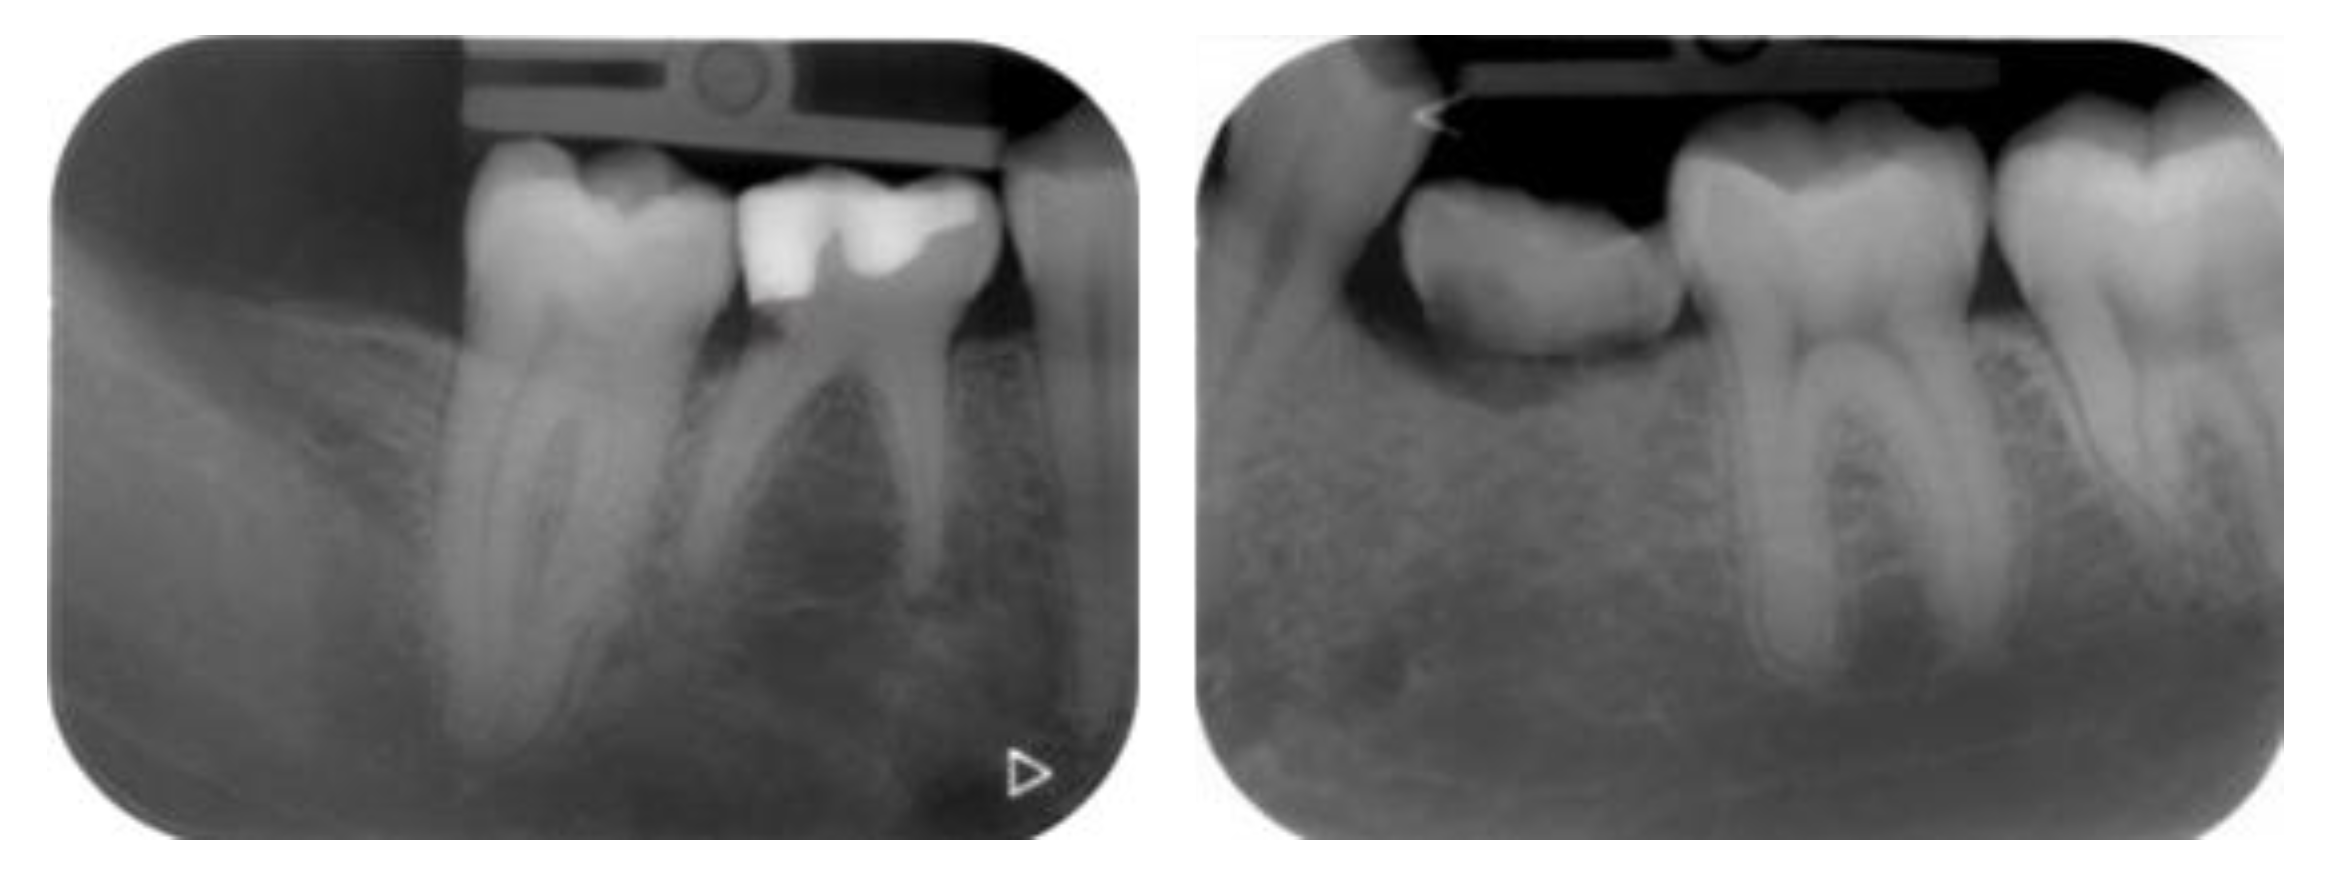

2.5. Individual Cases Description

- Case 1:

- Case 2:

- Case 3:

- Case 4:

- Case 5:

3.1. Clinical Results

3.2. Marginal Bone Level Outcomes